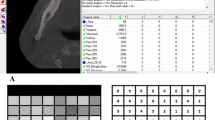

Preparation of images for analysis was performed in four stages (Fig. 1):

All these operations were carried out in ImageJ, the intended program for image processing and analysis. For all RVG images, rectangular regions of interest with similar dimensions were selected on both sides of the implant. Based on the literature, a bilinear interpolation method was used for the rotation [33, 37]. Histogram operations were used to attempt improve the quality digitized image [17, 20]. The images after processing in ImageJ were then analyzed in the Qmazda program. No normalization was performed with this program. As a result of actions in this program, almost 600 texture features values were extracted on the basis of ROI of each image.

The values of the parameters from Tables 1, 2 and 3 were normalized so that the average values of healthy tissue are \(100\%\) and for the remaining stages they were properly calculated as its percentage content. The data normalized in this way are presented in Tables 4, 5 and 6.

On the basis of Tables 5 and 6, a graph was created to visualize the comparison of percentage of normalized values of the average of parameters achieved for the upper jaw and mandible for the Replace implant (Fig. 2).